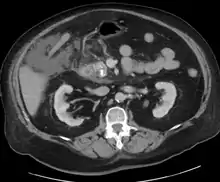

A contrast-enhanced CT scan is usually performed more than 48 hours after the onset of pain to evaluate for pancreatic necrosis and extrapancreatic fluid as well as predict the severity of the disease. CT scanning earlier can be falsely reassuring.